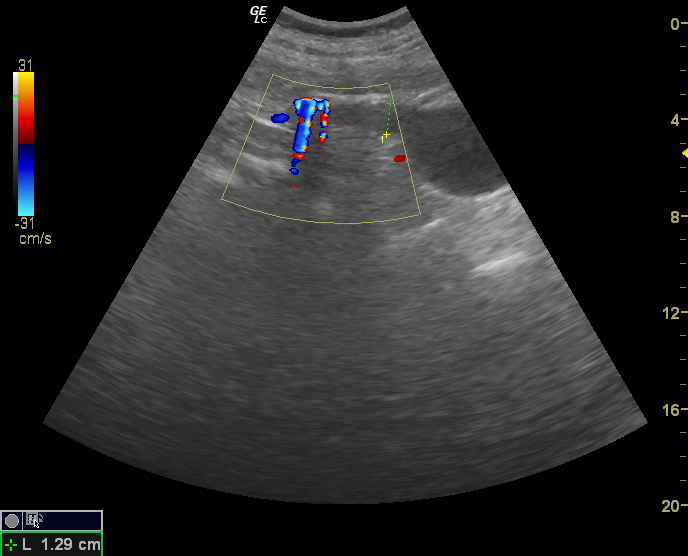

Вот такой случай МКБ с конкрементами в почке и мочеточнике и

роль артефакта мерцания в их уз-диагностике: